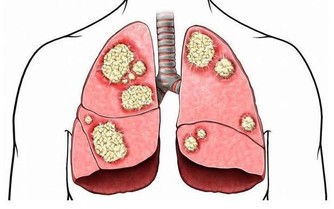

“空調腿”是指室內開啟空調後,地面水平溫度最低,人的雙腿長期低暴露在外,

容易受涼刺激,出現雙腿酸痛,嚴重時膝關節疼痛、腫脹,使人難以忍受。

絕大多數“空調腿”是膝關節受寒冷刺激導致的滑膜炎、滑囊炎以及腿部肌肉受冷痙攣。